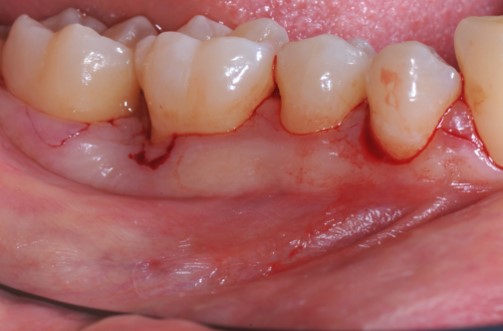

07/22 - Intra-operative view reveals deep non-contained intrabony defects distally to tooth 46 (PPD 10 mm) and on the mesial aspect of tooth 45 (PPD 6 mm). Buccal view.

Deep intrabony defects treated using Straumann® Emdogain® - Dr. M. Stefanini